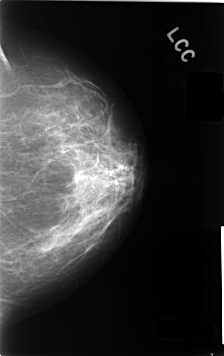

C_0404_1.LEFT_CC

LEFT_CC LINES 4624 PIXELS_PER_LINE 2912 BITS_PER_PIXEL 12 RESOLUTION 50 NON_OVERLAY